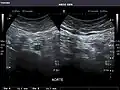

Aorta

Aorta: Visualized portions normal in caliber, 16 x 15 mm.